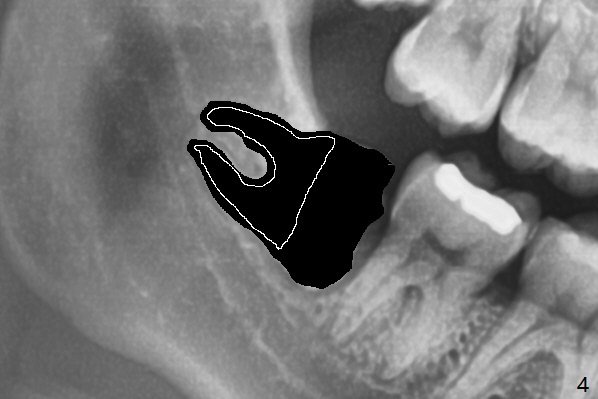

A 22-year-old man with poor oral hygiene requests extraction of the lower right 3rd molar. The buccal gingiva of the 2nd molar is erythematous and edematous (Fig.1 *). There is tenderness between #31 and 32 with severe bone loss (Fig.2 *). After extraction and debridement (Fig.3), Osteogen plug is inserted into radicular portion of the socket (Fig.4 white outline), while allograft is placed coronally (Fig.5, 7), covered by Collagen plug (Fig.6) before suturing. The bone fills the whole socket 1 year postop (Fig.8); there is no root surface exposure at #31. The bone fills the whole socket of #32 one year postop (Fig.8); there is no root surface exposure at #31.